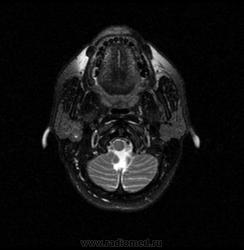

06.06.2011 МРТ - головы и шеи.

Пацентка 36 лет, с жалобами на припухлось в околоушной области справа.

В глубокой доле  правой околоушной железы  на фоне неизмененной паренхимы зона  гетерогенного по Т2, гипоинтенсивного по Т1  с единичными гиперинтенсивными включениями.При контрастировании- накопление контраста диффузное неоднородное и по периферии.Рискну предположить злокачественное образование ( аденокарцинома) с низкой степенью злокачественности( есть капсула, экспансивный рост).Сильно не расстреливайте.

Проблема в том, что перед челюстно-лицевым хирургом стоит распространенность любого объемного процесса, в данном случае все упирается в возмможную травму лицевого нерва и конечно же с дальнейшим его парезом, а ведь женщина  еще молодая. Образование имеет тонкостенную оболочку, по структуре неоднородно, с наличием кальцината, при этом МР-сигнал от окружающих анатомических структур(как костных так и мышечных) не изменен, т.е. об инфильтративном росте речи не идет, в какой то степени доброкачественное. В конкретном случае лицевой нерв с ретромандибулярной веной просто несколько оттеснен.

По гистологии аденома околоушной слюнной железы, но после удаления пока сохраняется парез лицевой мускулатуры, возможно временный.